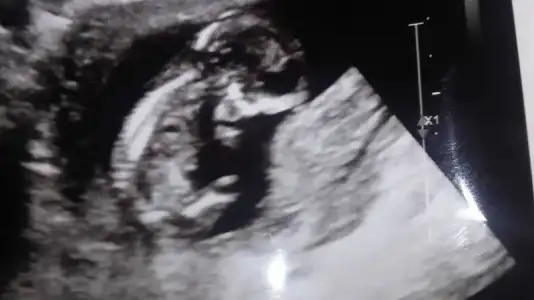

kız mı erkek mi tahmini yapamicam ama burnu çok güzel bi bebek olucak maşallahArkadaslar bugün doktor komtrolunden geldik. Doktor burun ve enseye bakti hersey normal gorunuyor cok sukur. Kan testi sonucum haftaya cikacak. Cinsiyet tahmini de yapti tam emin olmayarak. Siz de bakar misiniz ne tahmin edeceksinizEki Görüntüle 2040547